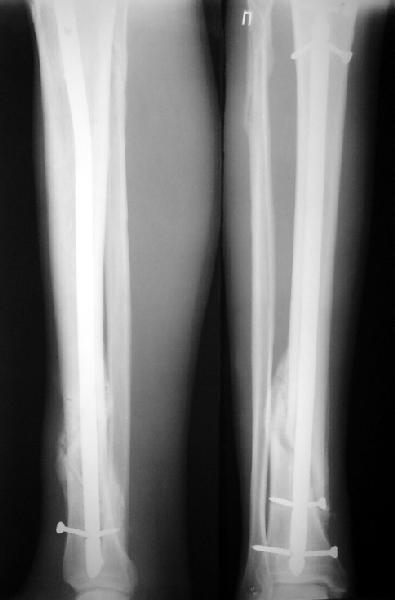

Ok. А также и следующий, в 3 месяца.

Это наглядная демонстрация возможности ранней полной нагрузки при нестабильном по оси повреждении, причем не в самых благоприятных механических условиях - при плохом сопоставлении, со слабым фиксатором.

Вы пишите:"Это наглядная демонстрация возможности ранней полной нагрузки при нестабильном по оси повреждении, причем не в самых благоприятных механических условиях - при плохом сопоставлении, со слабым фиксатором".

Это зависит от стандартов лечения, принятых у Вас.